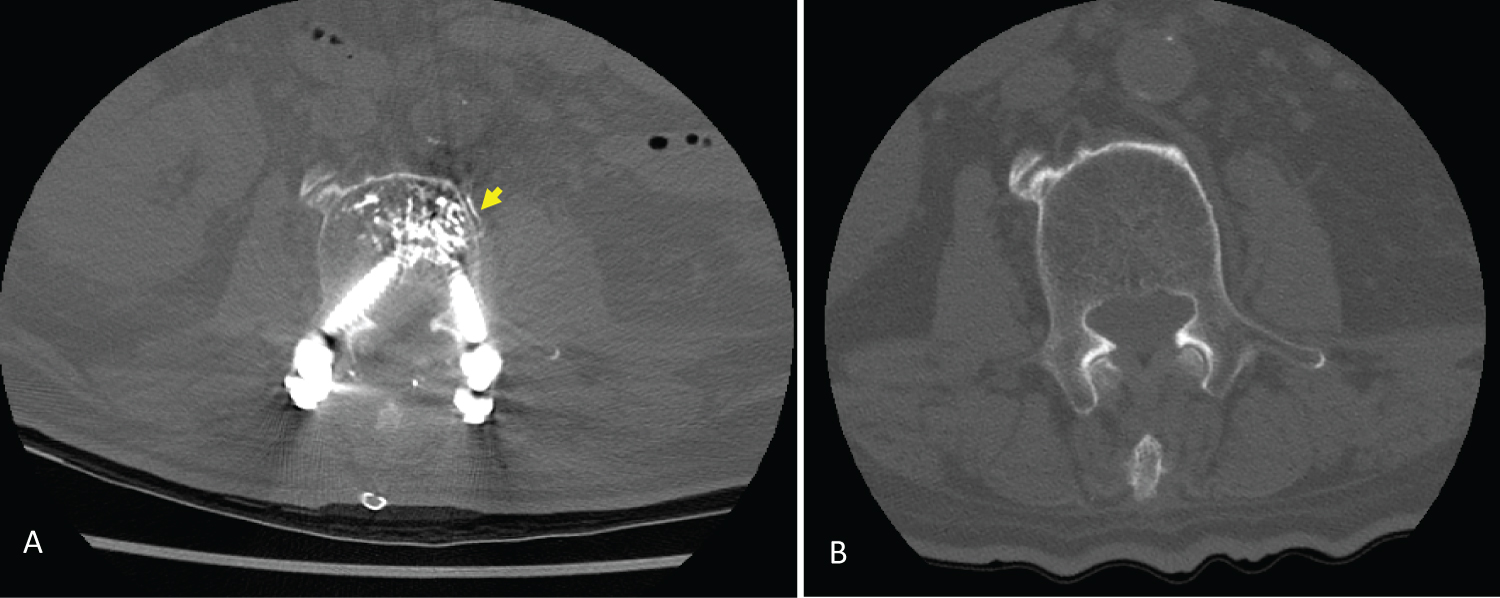

His respiratory condition improved transiently to a P/F ratio 138.29 (96.8/0.7), but worsened on the next day. PaO2 on an FiO2 of 1.0 dropped to 43.9 mmHg, and VV-ECMO support was indicated. The VV-ECMO implantation was performed by a cardiovascular surgeon smoothly on the eleventh postoperative day. Sedative agents and heparin infusion began after VV-ECMO implantation. The activated partial thromboplastin time was around 40 to 60 seconds. The patient's lung condition did not improve despite the full support of VV-ECMO. Follow-up chest CT on the twenty-first (Figure 4) showed further consolidation of bilateral lung parenchyma and persistent right-sided pneumothorax. A grave prognosis was apparent, and the patient expired within a half hour after withdrawal of VV-ECMO support on the forty-sixth postoperative day.

Figure 4: Chest computed tomography on the twenty-first postoperative day showed pulmonary cement emboli (arrow), further consolidation of bilateral lung parenchyma, and persistent right-sided pneumothorax. View Figure 4